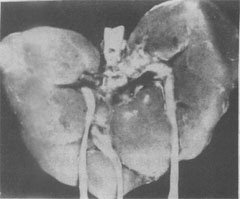

图6-3 18三体(Edwards)综合征的畸形肾

图示马蹄状融合肾及额外输尿管